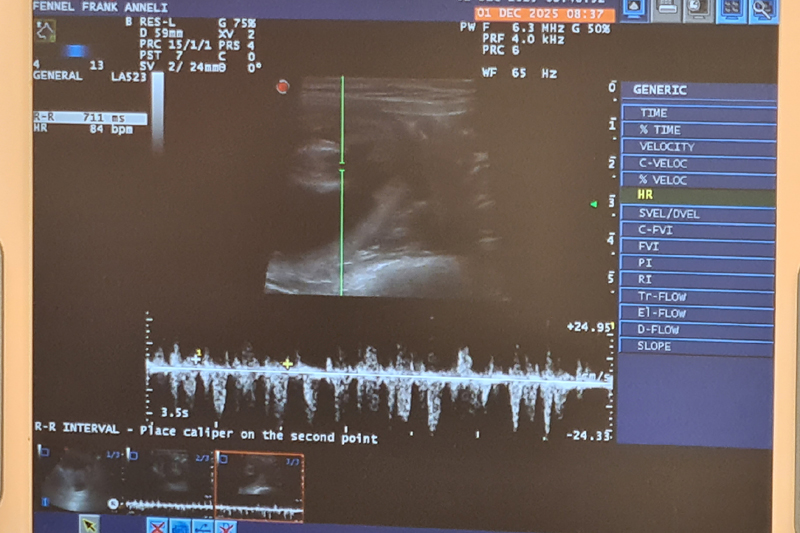

Ultraljud på måndag

På måndag gör vi ultraljud för att se om Fanny har valpar i magen. Håll tummarna!

Inga valpar....

Fennel är tyvärr inte dräktig. Vi har tyvärr haft otur igen med fryst sperma. Det är så trist för det finns så många fantastiska hanar där ute i världen

som jag så gärna vill ha i min avel. Men vi ger inte upp så lätt!